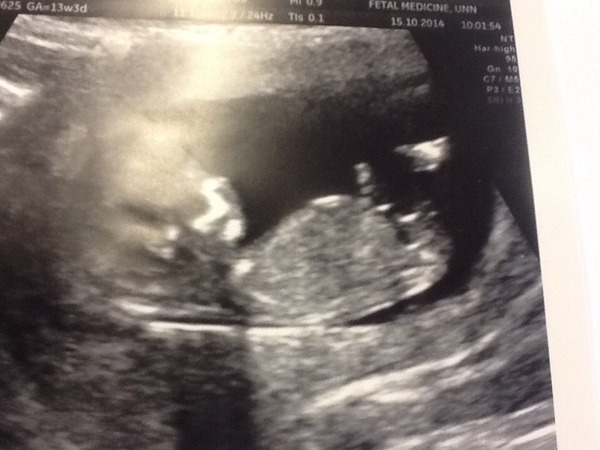

Great news about the 12 weeks scan, I cannot wait to have mine, I've been feeling like crud all day again today which I'm taking as a good thing for now.